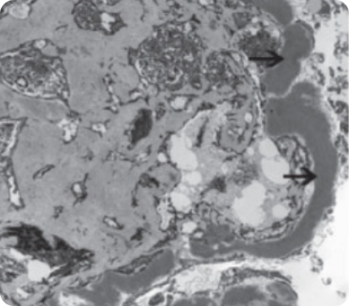

C3-гломерулопатия (C3ГП) представляет собой хроническое редкое заболевание почек, характеризующееся нарушением системы комплемента и отложением фракции C3 в биоптате почечной ткани. Это состояние включает два подтипа: болезнь плотных депозитов (БПД) и С3-гломерулонефрит (C3ГН), различающиеся по локализации отложений C3b, обнаруживаемых при электронной микроскопии.

БПД:

• Мезангиальные и внутримембранные, протяженные, электронноплотные, осмофильные отложения6—8.

• Наблюдается у 33% пациентов с С3ГП1.

Электронная микроскопия10

Электронная микроскопия

• Электронно-плотные отложения в мезангии вдоль ГБМ.

• Необходима электронная микроскопия для однозначного определения БПД и C3ГН1.